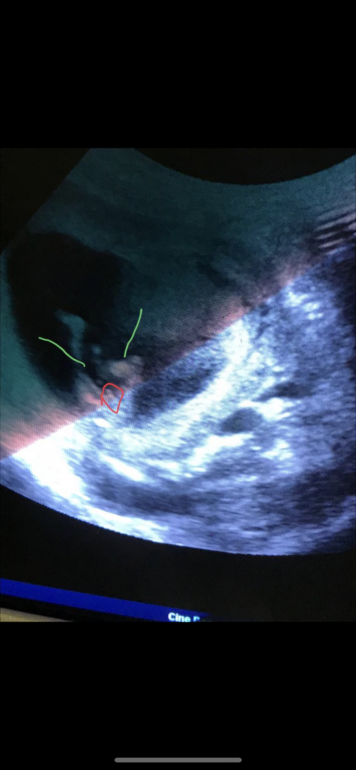

Добрый день ,была на скринингн ,сказали 90% мальчик )) но пока это не 100,потому что срок не такой уж и большой )) вот фото )) надеюсь это наш сыночек🙏🏻 Через неделю схожу уже точно отпишусь )

Красным это ножки )))

Зелёным ножки обозначила ,в кружочек наши 90% надеюсь это сыночек 🙏🏻